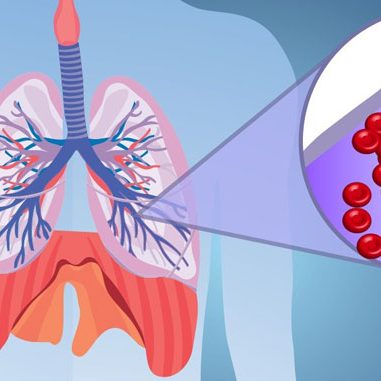

مقدمه: جنگ سیگارهای سنتی و مدرن در دنیای امروز، با ظهور سیگارهای الکترونیکی (ویپینگ) این سؤال مطرح میشود که آیا این محصولات واقعاً جایگزین ایمنتری برای سیگارهای معمولی هستند؟ در این مقاله جامع، به مقایسه علمی عوارض این دو نوع محصول دخانی بر اساس آخرین تحقیقات ۲۰۲۳-۲۰۲۴ میپردازیم. بخش اول: ترکیبات و مکانیسم عمل سیگار…